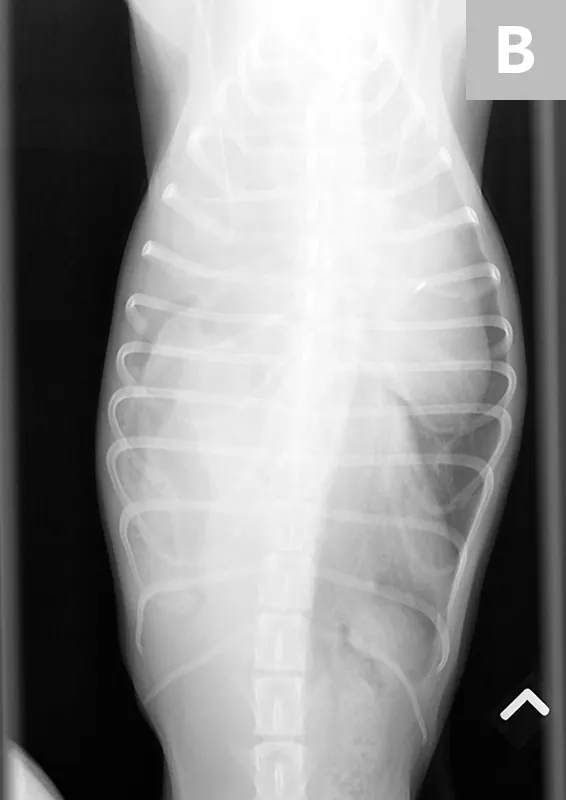

FIGURE 3A

(A) Right lateral and (B) dorsoventral radiographs of a 2-year-old spayed dog following blunt motor vehicle trauma. The diaphragmatic margins are obscured—most notably on the right side, where there is herniation of abdominal viscera into the thoracic cavity consistent with diaphragmatic hernia. The presence of tubular gas suggests some of the herniated abdominal structures are intestinal.